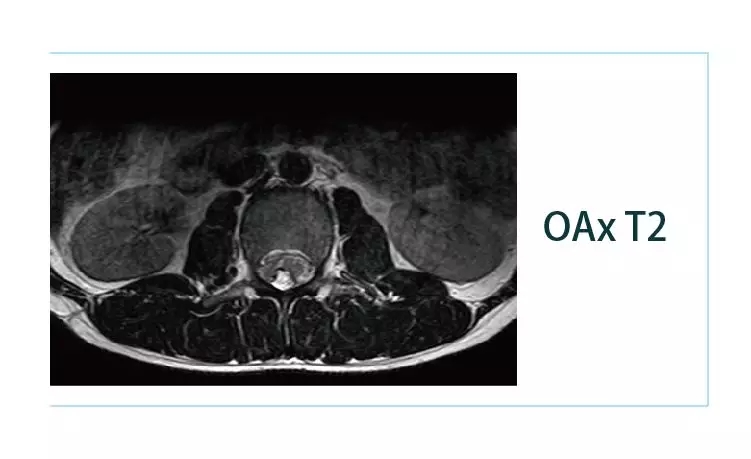

【朗润影像档案】20190225磁共振影像病例结果讨论